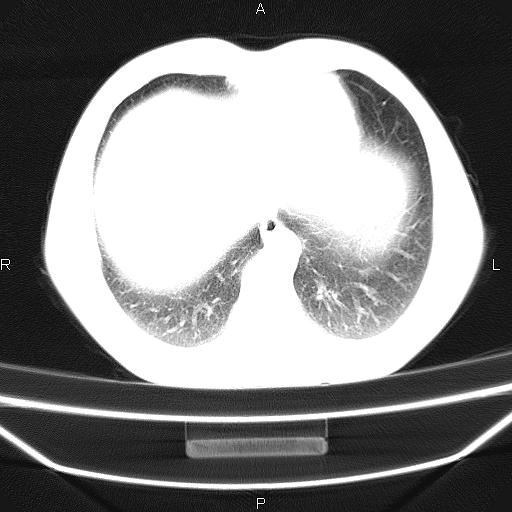

标题: CT26599:男,40岁。间断发热,咳嗽二十余日。体温最高达38.9 [打印本页]

标题: CT26599:男,40岁。间断发热,咳嗽二十余日。体温最高达38.9

患者,男,40岁。间断发热,咳嗽二十余日。体温最高达38.9° 在当地诊所抗炎治疗三天后体温降至正常,患者自行停药。今又发热。胸片示,左下肺阴影。

标题: 左下肺片状高密度影

左下肺片状高密度影,境界模糊,密度不均,考虑感染性病变可能性大,建议抗炎治疗后复查。左肺门增大,不除外占位性病变,必要时支气管镜检。